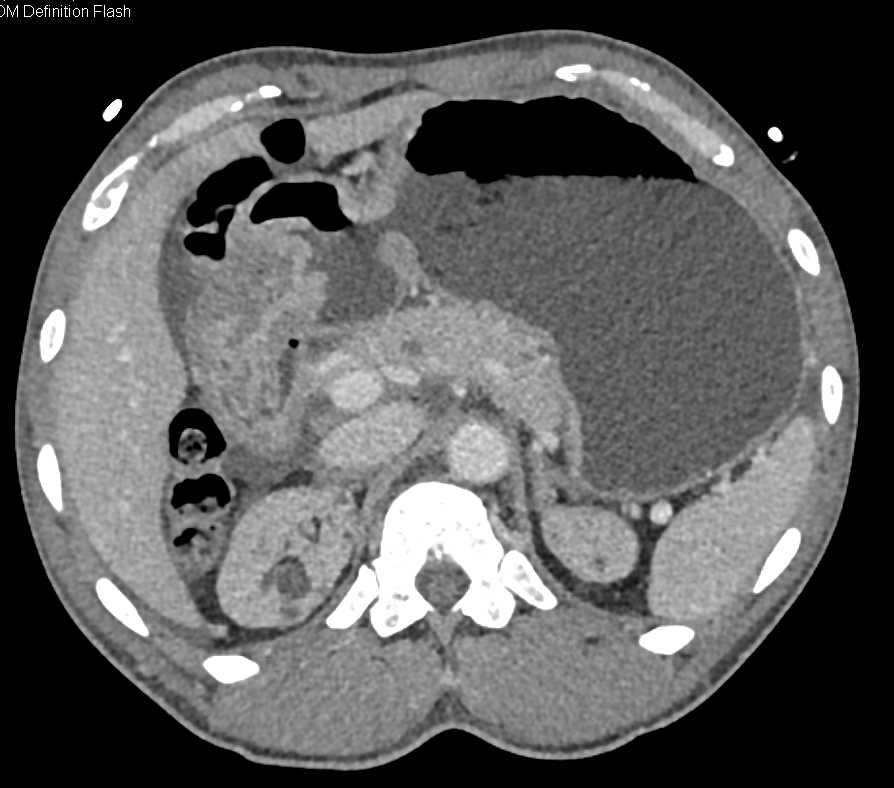

Antral Carcinoma with Stent in Antrum and Positive PET Scan